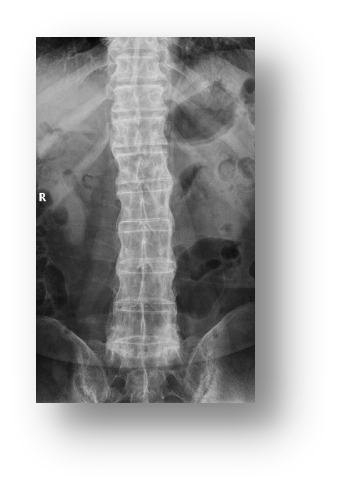

下图的X线平片考虑哪种常见疾病

选项:

A: 退行性骨关节病

B: 弥漫特发性骨质增生症(DISH)

C: 强直性脊柱炎

D: 脊柱结核

答案: 【 强直性脊柱炎】